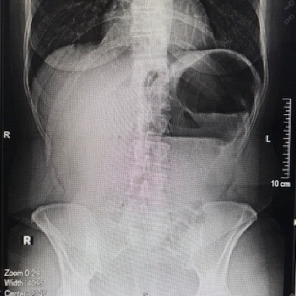

Introduction: Volvulus of the caecum, ascending colon and first third of the transverse colon is a very rare surgical emergency. Timely diagnosis and intervention can avert serious complications. Case Report: A 54-year-old woman presented to the emergency department with colicky epigastric pain radiating to the left iliac fossa that lasted for 12 h. Vital signs were stable upon arrival at the hospital. Physical examination revealed that left abdomen and suprapubic fullness and bowel sounds were recorded, and rebound tests were negative. Laboratory results were neutrophils: 78% (35%-72%), lymphocytes: 16% (20%-45%), HB: 11 g/dL (12-16), HCT: 33% (36%-48%); all the rest were normal. Furthermore, computed tomography revealed a distended close of the large bowel extending from the left hypochondrium to the left iliac fossa. During explorative laparotomy, volvulus of the first third of the transverse, ascending colon and caecum was detected. Because the viability of the bowel wall was compromised, right extended hemicolectomy was performed with consequent ileotransverse anastomosis. The postoperative period was uneventful, and the patient was discharged on the fourth postoperative day. Conclusions: Expeditious diagnosis and early intervention of very rare surgical emergencies such as ascending colon volvulus may avert disastrous complications.

Abstract Image